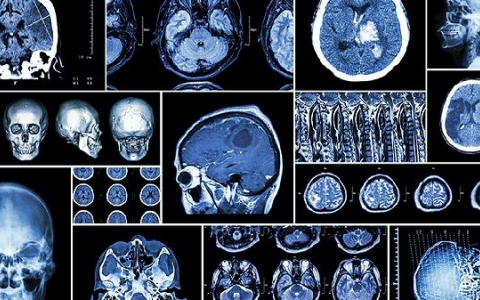

脑梗死

脑梗死是脑血液循环障碍,由于缺血、缺氧引起局限性脑组织缺血性坏死或软化,通常出现头痛、偏瘫、意识障碍等症状。对于急性脑梗死患者,可根据医生的建议选择阿替普酶、尿

缺血性脑梗死后遗症脑梗死或缺血性中风,是一种非常严重的疾病。由于人脑血液供应障碍、脑缺血、缺氧,局部脑组织坏死软化。通常会出现脑血栓形成、脑梗死或脑栓塞,严重危